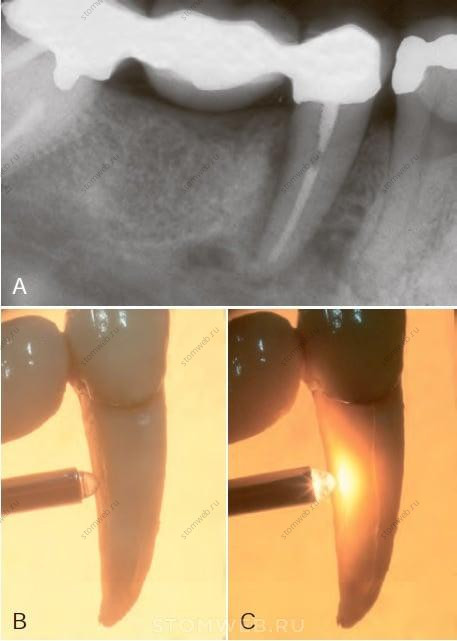

РИС. 21-10 Рентгенограмма, показывающая потерю костной ткани в связи с вертикальным переломом корня. Зуб 4.5 был лечен эндодонтически и восстановлен с использованием короткого штифта. Через два года пациент начал отмечать дискомфорт и чувствительность во время жевания. Изначально никаких рентгенографических признаков обнаружено не было. Так продолжалось в течение 9 месяцев, по истечении которых на рентгенограмме (А) была обнаружена обширная резорбция кости, и зуб был удален. А) Обширный очаг просветления костной ткани вдоль дистальной поверхности корня. В) Зуб удален, но щечный ВПК не очевиден. С) Просвечивание ярким узким пучком света отчетливо демонстрирует ВПК.

РИС. 21-11 Деструкция костной ткани в связи с вертикальным переломом корня на прицельной рентгенограмме. Зуб 4.5 после эндодонтического лечения был восстановлен без штифтовой конструкции. Через год пациент начал жаловаться на чувствительность с язычной стороны. Через три месяца сделали рентгеновский снимок (А) и удалили зуб. Вдоль дистальной поверхности корня обнаружился небольшой участок просветления костной ткани. Зуб был удален, но при визуальном осмотре явного перелома корня не выявилось (В). Просвечивание корня удаленного зуба интенсивным, но узким пучком света позволило четко визуализировать вертикальный перелом корня (С,D).